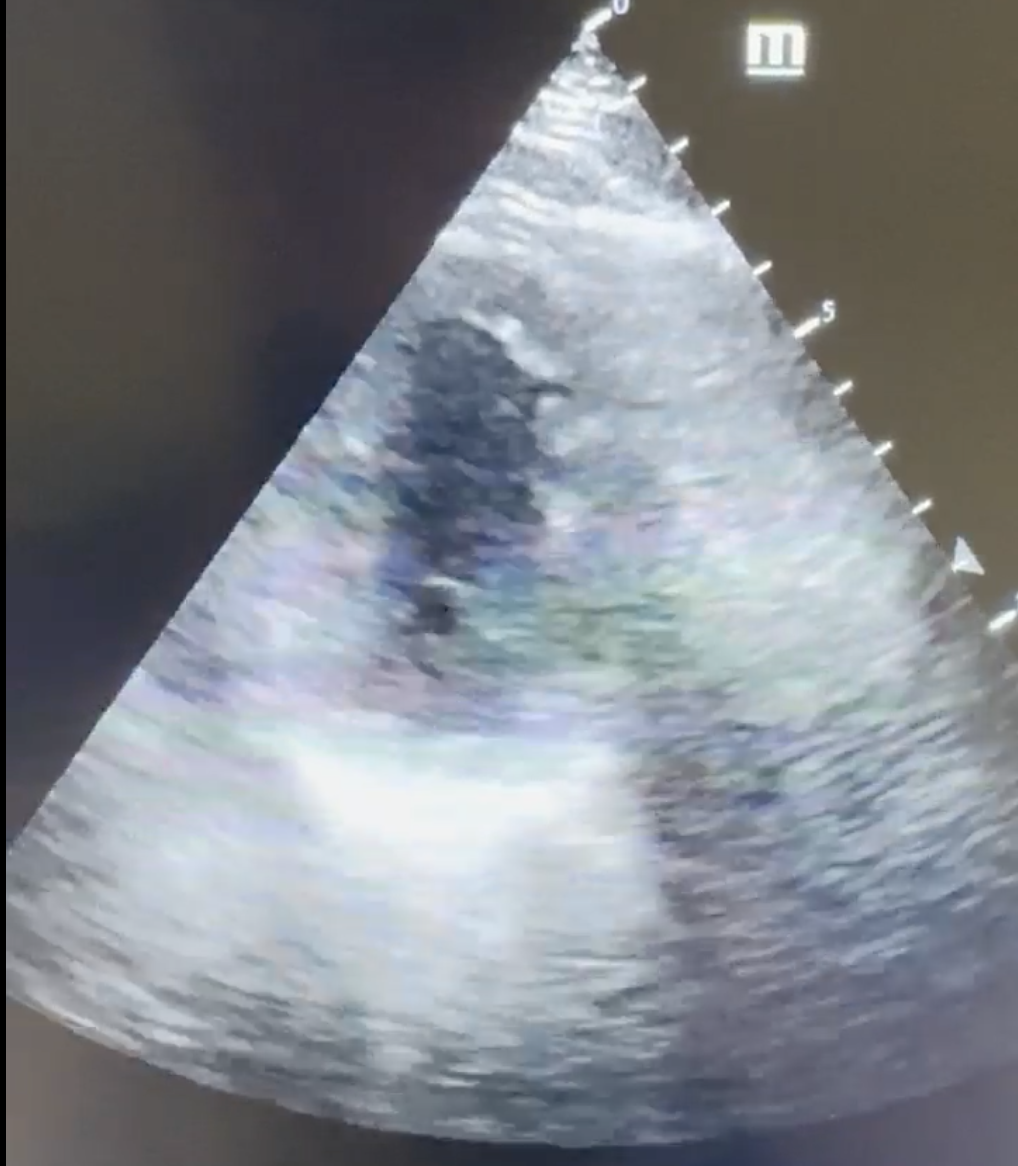

A 38-year-old male presents to a community hospital emergency department at 3 a.m. and a rapid response is called to the front of the hospital. You respond, and the patient is alert but diaphoretic, weak, and displaying Levine’s sign (a fist clenched over his chest). His wife states that the chest pain started about 30 min prior to arrival. The patient is brought to your resuscitation bay, and his vital signs are as follows: BP 145/98, HR 99, RR 18, O2 93%. You ask for an EKG when then tech informs you that both of the EKG machines in the ED are broken, and we currently have no way of obtaining a tracing. What do you do in this scenario?